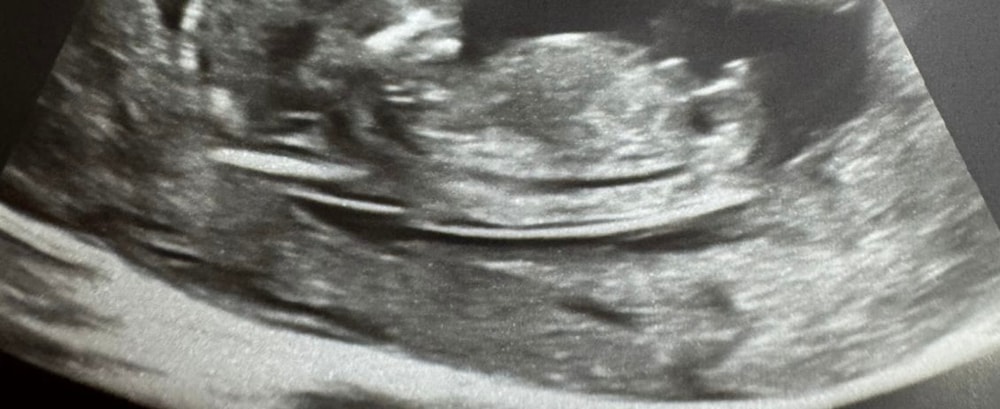

Нина в Клуб беременных 5 месяцев Девочки на кого похож? Пол малыша Интересно на кого больше походит, девочка или мальчик?)) Посмотрите еще 20 записей на эту тему Отменить Ответить Стефания Девочка 12.07.2025 Ответить Кактусеныш Девочка 12.07.2025 Ответить Светлана На мальчика похож 12.07.2025 Ответить Людмилка Как по мне так это мальчишка 🥰 12.07.2025 Ответить Тата На мальчика бугорок больше похож. Как Вы выдержали и не сдали кровь на определение пола? 😁 12.07.2025 Ответить Нина Тата, не знаю😅 12.07.2025 Ответить Кэт Ну тут спорно, мне вроде мальчик, но если присмотреться то девочка 😁😃 12.07.2025 Ответить Дарья Мальчик 12.07.2025 Ответить Светлана Мальчик 12.07.2025 Ответить Нина Светлана, было бы круто после 3-х девочек 🫣 12.07.2025 Ответить Светлана Нина, скоро узнаете)) но половой бугорок все же под углом,так что есть шансы на мальчика 12.07.2025 Ответить Нина Светлана, спасибо 🌷 12.07.2025 Ответить Анна На мальчика больше похоже 12.07.2025 Ответить Jenny Я бы сказала, на девочку)) 12.07.2025 Ответить Пол ребёнка Китайский календарь Чаты Беременных Выберите чат: Январята-2026 Февралята-2026 Мартята-2026 Апрелята-2026 Майчата-2026 Июнята-2026 Июлята-2026 Августята-2026